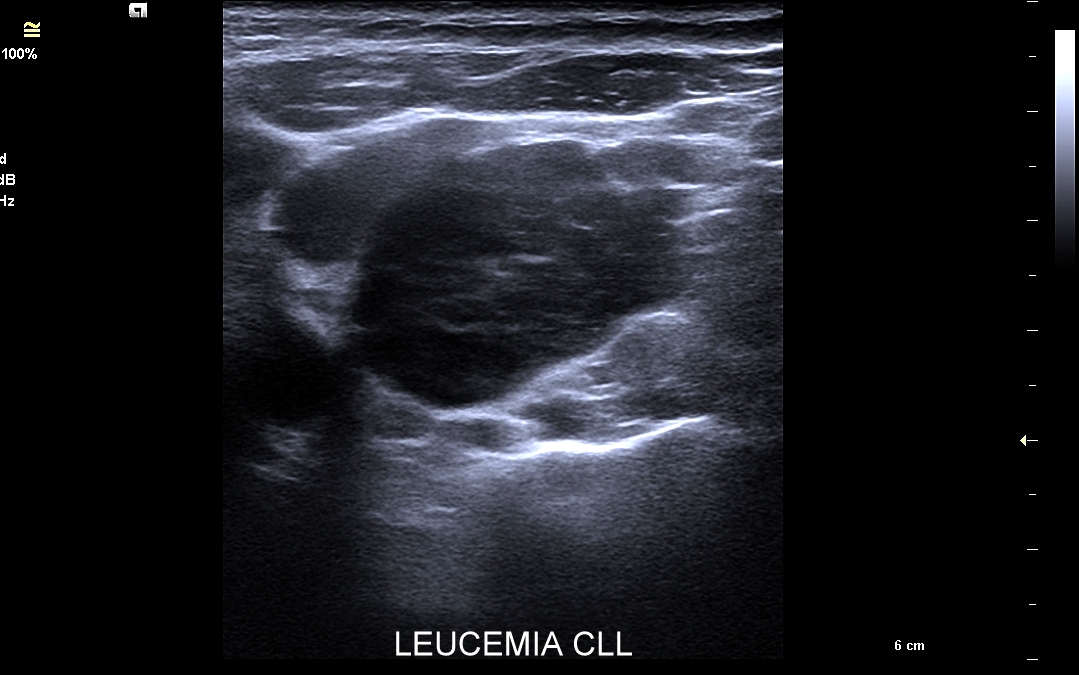

W przebiegu chorób, w których dochodzi do stymulacji układu odpornościowego, węzły limfatyczne ulegają powiększeniu. Przykładami są miejscowe lub uogólnione procesy zapalne i autoimmunologiczne, schorzenia infekcyjne bakteryjne, wirusowe, grzybicze i pasożytnicze. Węzły chłonne powiększać się mogą również w przebiegu białaczek i chłoniaków, a także w trakcie chorób nowotworowych, w których dochodzi do tworzenia przerzutów.

Badanie USG jest podstawową metodą obrazowania węzłów chłonnych. W jego trakcie ocenia się nie tylko wielkość węzłów, lecz także ich kształt, proporcje wymiarów, morfologię, czyli wygląd zewnętrzny oraz strukturę wewnętrzną, ich unaczynienie, spoistość, a także tkanki otoczające. W trakcie interpretacji badania pod uwagę bierze się również zbierany od pacjenta wywiad chorobowy oraz wyniki innych badań obrazowych i laboratoryjnych takich jak morfologia, OB, CRP, żelazo, ferrytyna, TIBC, innych parametrów infekcyjnych, a także onkologicznych. Ultrasonografia węzłów chłonnych jest procedurą bezpieczną i dokładną. W Pracowni dr Szczepańskiego węzły chłonne oceniane są nowoczesną metodą MPUS (multiparametryczne badanie USG), w szczególności z zastosowaniem trybów mikrounaczynienia i elastografii.

Do powiększenia węzłów chłonnych szyi, stanu określanego jako limfadenopatia, dochodzi najczęściej w przebiegu chorób zakaźnych górnych dróg oddechowych, wirusowych i bakteryjnych. Inne przykłady przyczyn limfadenopatii szyjnej obejmują ropne choroby zębów, migdałków i zatok przynosowych; odczyny w chorobach autoimmunologicznych, np. w chorobie Hashimoto i Sjögrena; a także rozrostowe schorzenia układu hematologicznego (białaczki i chłoniaki) i choroby nowotworowe jak np. rak tarczycy, krtani, migdałka, czy języka. Należy mieć na uwadze, iż w przypadku podejrzenia chorób układu krwiotwórczego oraz mononukleozy zakaźnej, oprócz węzłów chłonnych, niezbędne jest również badanie USG wątroby i śledziony. W części przypadków, gdy podejrzewa się możliwość choroby nowotworowej lub w celu jej wykluczenia, lekarz może zalecić rozszerzenie diagnostyki obrazowej na inne obszary ciała.